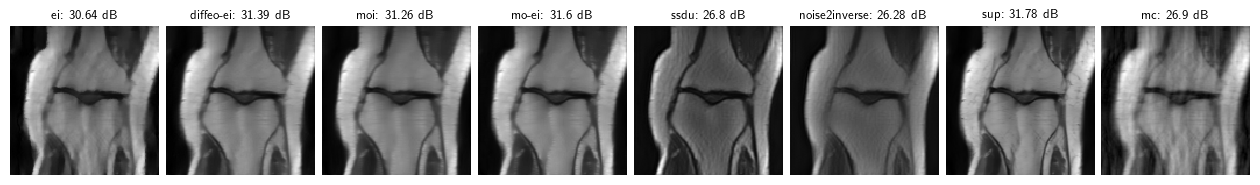

Note: these results are for a toy problem on 128x128 images trained for 50 epochs. For full benchmark results on full datasets see the paper “Benchmarking Self-Supervised Methods for Accelerated MRI Reconstruction”.

pd.DataFrame.from_dict(results, orient="index", columns=("PSNR", "PSNR no learning")).sort_values('PSNR', ascending=False).round(3).transpose()| sup | mo-ei | diffeo-ei | moi | ei | mc | ssdu | noise2inverse | |

|---|---|---|---|---|---|---|---|---|

| PSNR | 31.779 | 31.601 | 31.388 | 31.260 | 30.643 | 26.896 | 26.796 | 26.282 |

| PSNR no learning | 26.897 | 26.897 | 26.897 | 26.897 | 26.897 | 26.897 | 26.897 | 26.897 |